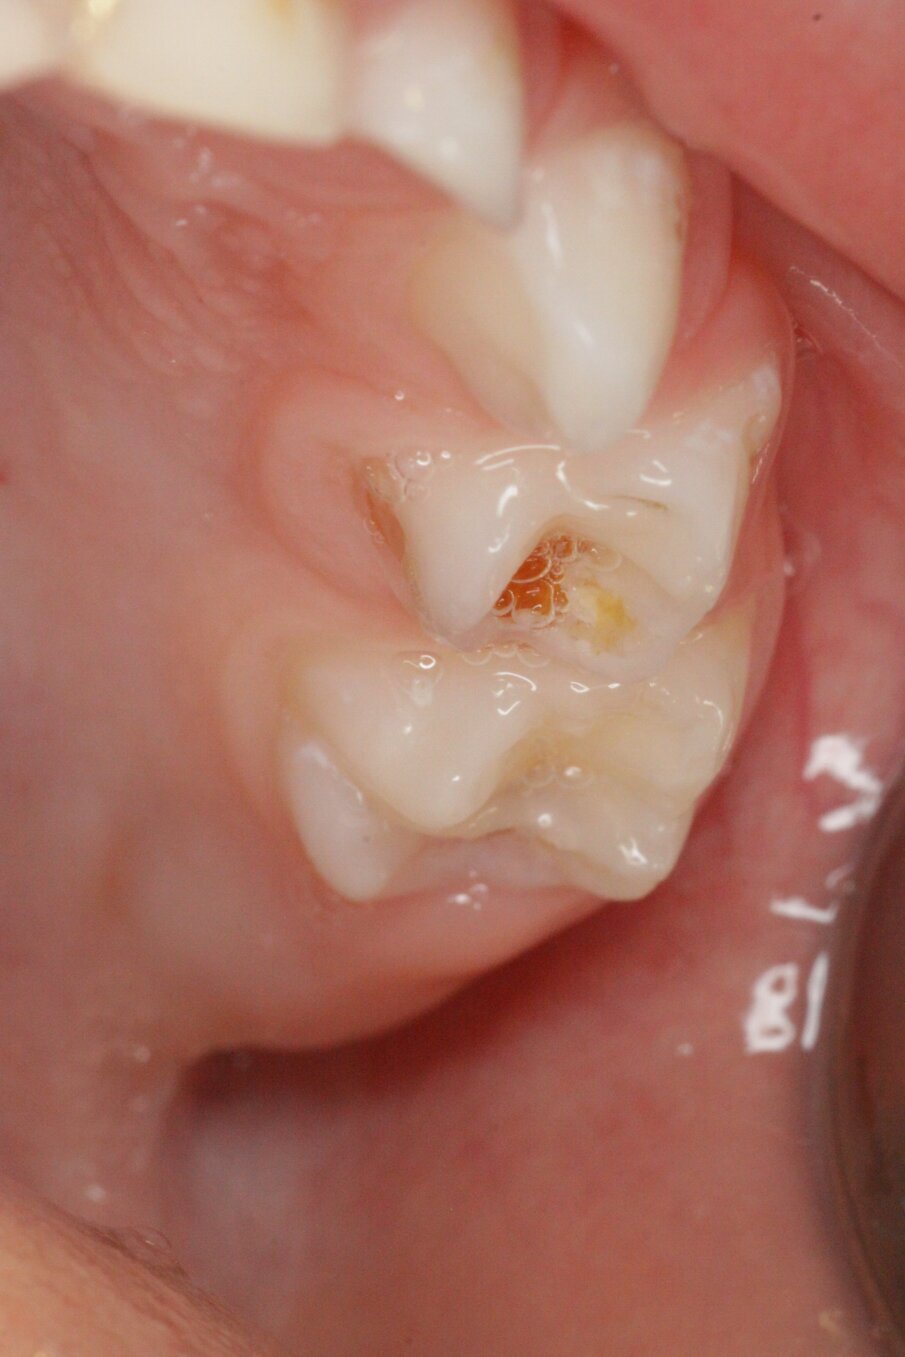

Er wordt bij periodiek mondonderzoek weinig plaque aangetroffen. Sommige laesies zijn inactief en andere worden of blijven actief (afbeelding 3a-c). De 75 werd na een half jaar van een Atraumatic Restorative Treatment (ART)-restauratie voorzien wegens gevoeligheid. Na 2 jaar trad ’s nachts pijn op aan de 64, maar deze verdween weer. Achteraf was het beter geweest als de 64 ook met ART was gerestaureerd (afbeelding 4a-b). Moeder is tevreden over de behandeling na 4 jaar, maar wij zullen nog beter ons best doen om meer zicht te krijgen op de mondverzorging thuis en daar de behandeling op afstemmen. Hoe dan ook, een narcosebehandeling is deze jonge patiënte gelukkig bespaard gebleven.

Afbeelding 3a. Cariëslaesies onderkaak rechts.

Afbeelding 3b. Cariëslaesies ruim half jaar later stabiel.

Afbeelding 3c. Cariëslaesie 64 na een half jaar nog actief.